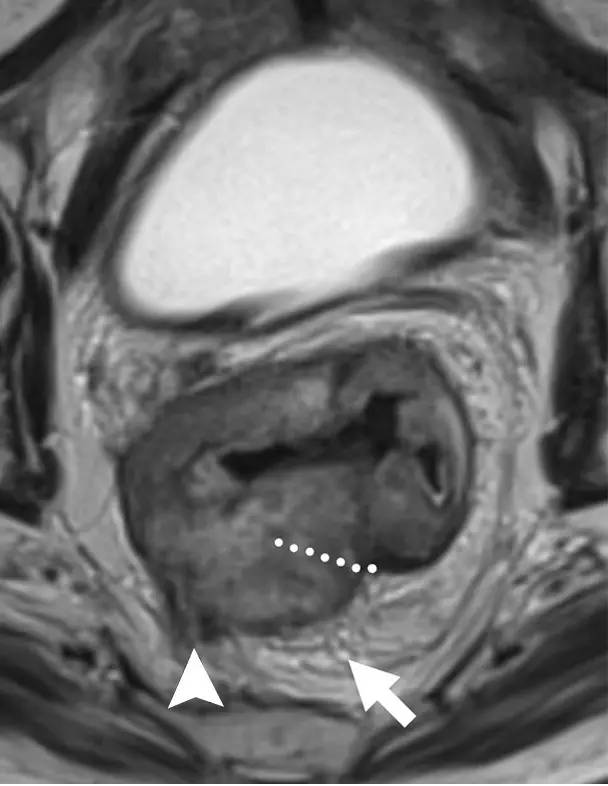

T3 分期,累及 MRF

在 T3 肿瘤的描述中,报告应包括肿瘤边缘和 MRF 之间的最短距离。MRF 阳性导致局部复发的风险增加(当肿瘤边缘和 MRF 之间的距离小于 1 mm 时,MRF 被认为是阳性)。

图 8 T3 直肠癌 MRF+